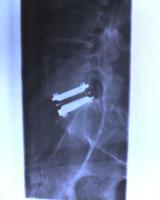

For those that are interested, here's a sideview x-ray of my artificial disc. It was taken in November 05, about 3 months post-op'. The chromium end plates show up well, the high density polyurethene insert in the middle obviously doesn't, although you can make out the metal strip that runs through dead centre.

I make no claims about what is the best approach to back surgery, or indeed, bearing in mind some comments in this interesting thread, whether surgery is the best / only approach. I do know that I was impressed by BNH (rather less so by Bumrungrad) and that the replacement disc approach has delivered everything promised .... so far.